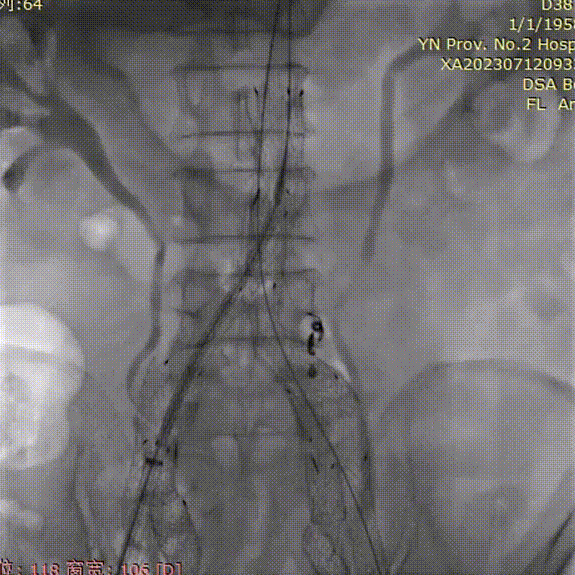

导管内手推造影,确认右髂内超选成功;

gore医疗怎么样「漫腹精论」双股动脉入路,纯腔内保双髂——GORE® EXCLUDER® 髂动脉分支型覆膜支架(IBE)治疗双侧髂总动脉_https://www.jmylbn.com_新闻资讯_第23张

右髂内支架通过IBE短腿后,整体往下拉IBE,将IBE短腿拉至右髂内动脉开口上方;